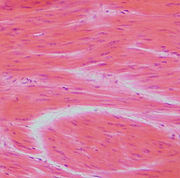

Příčně pruhovaná (kosterní) svalovina

Pod mikroskopem můžeme pozorovat žíhání, které je způsobeno pravidelným střídáním aktinu a myosinu v myofibrilách.

Kosterní svalstvo je tvořeno příčně pruhovanou svalovinou a obvykle se upíná ke kostem. Je ovladatelné vůlí a díky němu se tělo pohybuje. Je to například jazyk, svaly hlavy a končetin, ale i bránice, hlavní dýchací sval savců. Stavbu kosterního svalu je možné zkoumat na několika úrovních. Kosterní sval se na první pohled skládá z těchto částí:

Kosterní sval je tvořen dlouhými svalovými vlákny (až 40 cm), tvořené v podstatě jednou, ale mnohojadernou buňkou, takzvaným rhabdomyocytem. Vlákna jsou obalena řídkou vazivovou pochvou. Podélně uložená příčně pruhovaná vlákna se nazývají myofibrily, které umožňují kontrakci. Svalová vlákna se spojují ve snopečky a snopce (10–100 svalových vláken), které jsou kryté silným vazivovým obalem. Snopce se pojí ve svaly kryté pevnou a pružnou vazivovou blanou – fascií (povázkou). Na obou koncích svalu přechází fascie ve šlachy, které jsou pevně napojeny na kosti jako začátky a úpony svalů. Svalová i vazivová vlákna jsou elastická, umožňují až stoprocentní protažení své délky. Každé svalové vlákno (rhabdomyocyt) uvnitř v cytoplazmě obsahuje myofibrily, které je ještě příčně rozdělena na přepážky, sarkomery. Díky těmto sarkomerám dostaly příčně pruhované svaly svůj název.

Srdeční svalovina čili myokard (myokardum) podobá se příčně pruhované, buňky však nejsou tak dlouhé mají jen jedno buněčné jádro a jsou uspořádané ve více směrech. Není ovladatelná vůlí. Podměty ke stahování vznikají přímo v srdci. Tvoří téměř celou srdeční stěnu.

Hladká svalovina je evolučně původnější, u bezobratlých je často jediným typem svalové tkáně v jejich tělech. U savců je přítomna pouze jako vůlí neovladatelná svalovina stěn cév, trávicí trubice, žaludku, vývodů žláz, dělohy nebo svalů jako je vzpřimovač chlupu nebo svaly duhovky oka. Na podnět reaguje pomaleji než příčně pruhovaný sval. Hladká svalovina není tvořena vlákny, ale samostatnými buňkami vřetenovitého tvaru, v jejichž cytoplazmě myofibrily nejsou uspořádané jako u příčně pruhovaného svalu, takže ani pod mikroskopem nemůžeme pozorovat příčné žíhání.